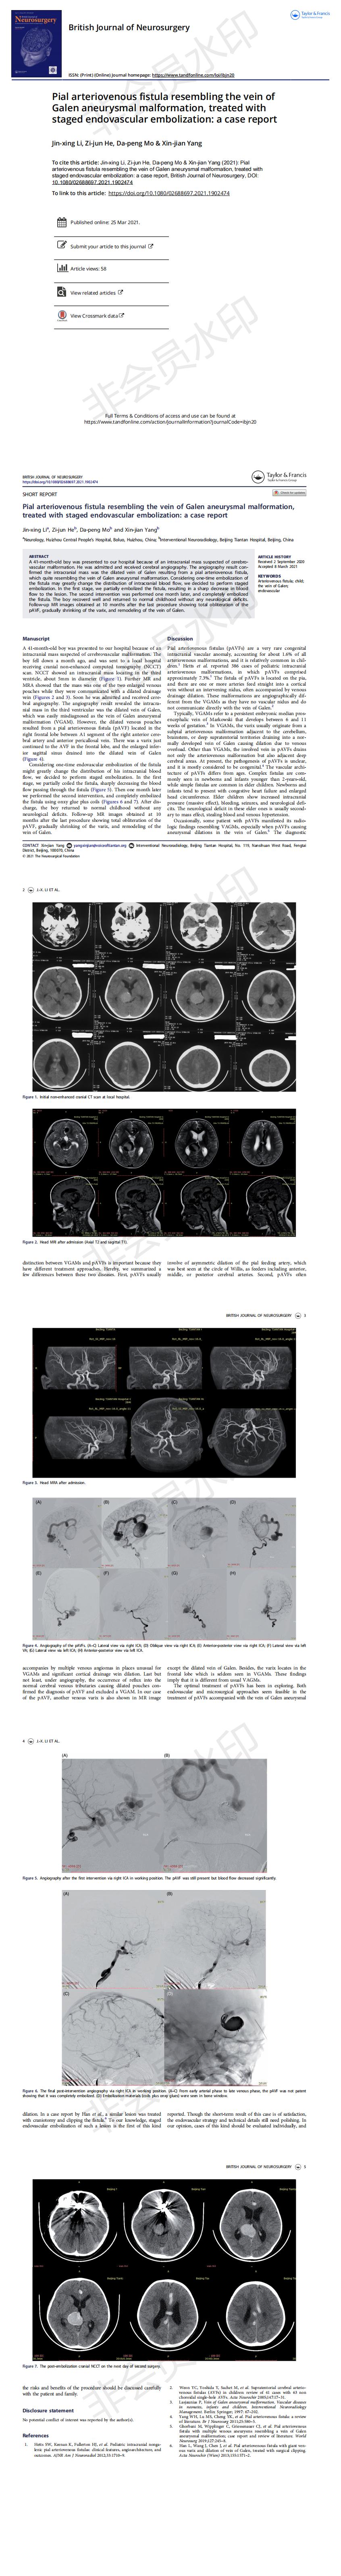

Pial arteriovenous fistula resembling the vein of Galen aneurysmal malformation, treated with staged endovascular embolization: a case report

李金星SCI論文-已掛網_00.jpg